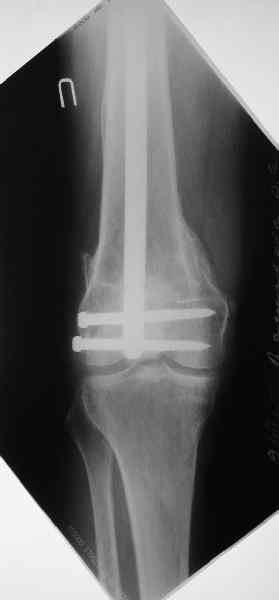

По прямой проекции неплохо. Что за стержень?

Антеградный остеосинтез при дистальных переломах бедра мы применяем давно, этот материал обобщен в канд. диссертации Александра Виноградского.

Предприятие ЦИТО выпускает доработанные нами гвозди, которые хорошо годятся для дистальных переломов, да и недороги. Можно вводть в дистальное овальное отверстие 3 винта, которые заклинивают друг друга.

Большеберцовые стержни отлично выполняют роль ретроградных бедренных. Конечно, которые не 9, а 12 мм в диаметре.

Примеры приложены.

Чтобы больной не смог сгибать колено, выстоять в сустав железо должно побольше значительно, чем на 1 мм. В приложении снимок с выстоянием ммм на 3, видна и функция колена. Хотя клиника импинджмента была, но даже не на один восклицательный знак. После удаления стержня проблемы и вовсе рассосались.